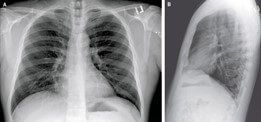

The most common way to look at the chest and lungs is through x-ray and Computed Tomography (CT) imaging. However, for COVID-19, x-rays don’t give you the information needed. The studies that are out, including ones from Lancet, The New England Journal, and the journal Radiology, concluded that due to the low sensitivity and specificity and a broad and varied method of interpreting chest x-rays, the scans tend to be vague. In addition, technicians use non-standard terminology, which can lead to inconsistencies in diagnosis and difficulty in following patients’ progress or decline.

Figure A. Chest x-ray of suspected COVID patient.

CT is still the gold standard for lung imaging, but it’s difficult to access a CT when you have a critical care patient. The volume of COVID patients, on top of limited access to CT machines, makes this method less than ideal for evaluating the lungs. Interestingly, in about 50 percent of patients, there are no findings between 0-2 days after the onset of symptoms of COVID. It takes about 3-5 days before CT findings are positive. When they are positive, they have bilateral peripheral and basal ground glass opacities (Figure B) in about 50-75 percent of patients. The distribution through the lungs is typically in the lower part of the lungs, but as the disease severity evolves, the CT findings can also be much more extensive.